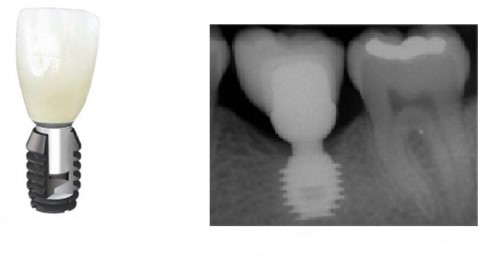

Когда мы говорим об ультракоротких (7 мм и менее) имплантах, то в первую очередь на ум приходит Bicon:

![]()

В далеком 1986 году американский профессор V. Morgan разработал концепцию субкрестальных коротких имплантов с фрикционной платформой. Последнее означает, что ортопедический интерфейс не имеет каких-либо антиротационных элементов (шестигранника и т. д.), а фиксация супраструктуры, коронки или абатмента, происходит путём «заклинивания»:

В этом есть, безусловно, революционность имплантов Bicon, их отличие от других современных имплантационных систем, в этом их главное преимущество и главный недостаток.